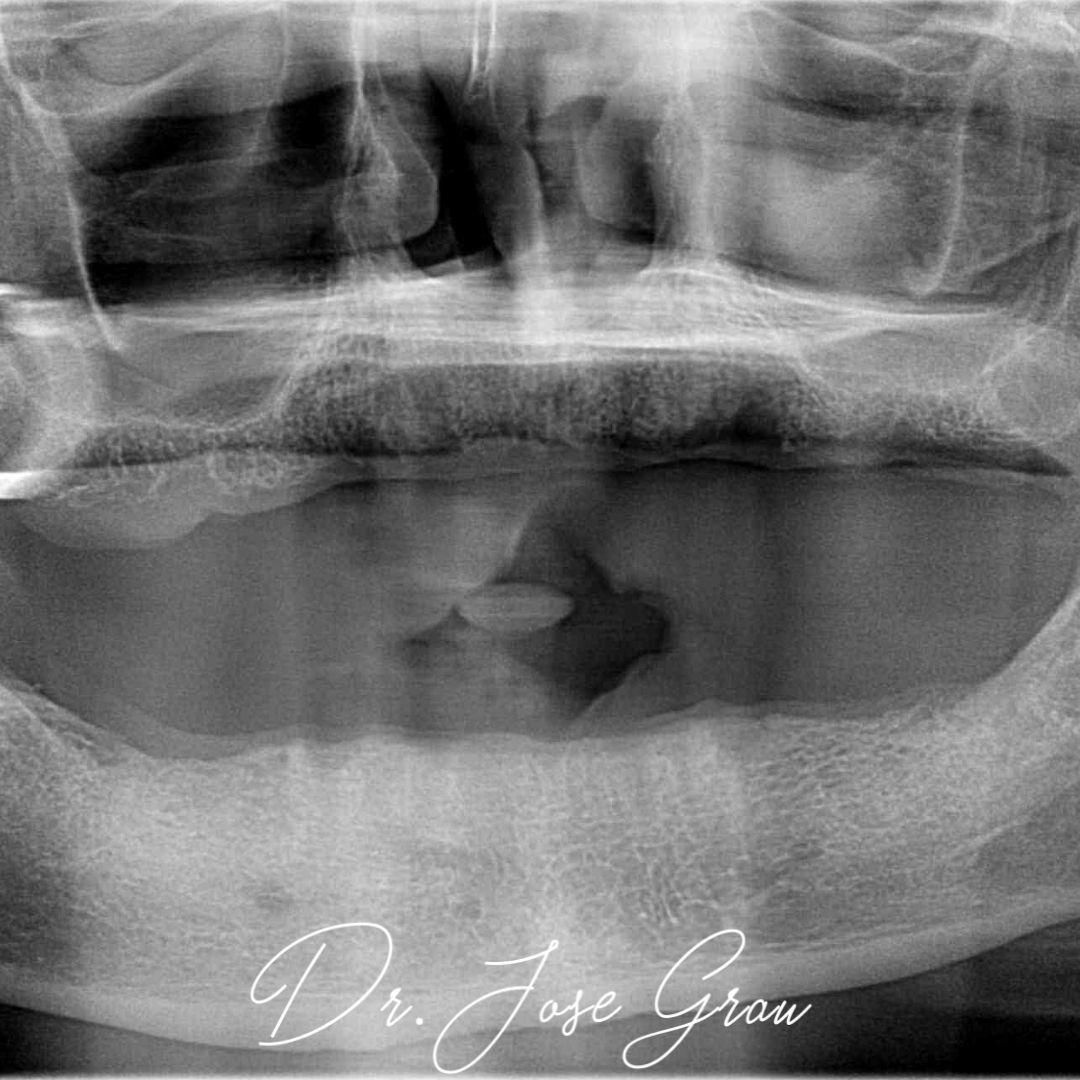

Rehabilitación bimaxilar flapless